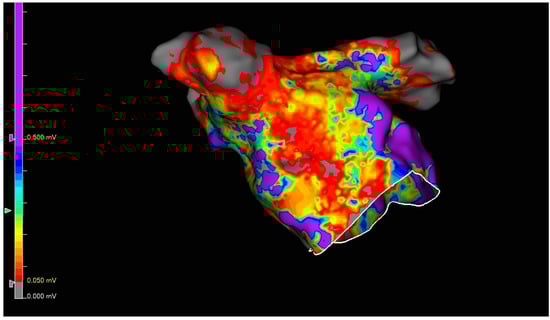

2.3. Endovascular Procedure

3.3. Acute Procedure Results